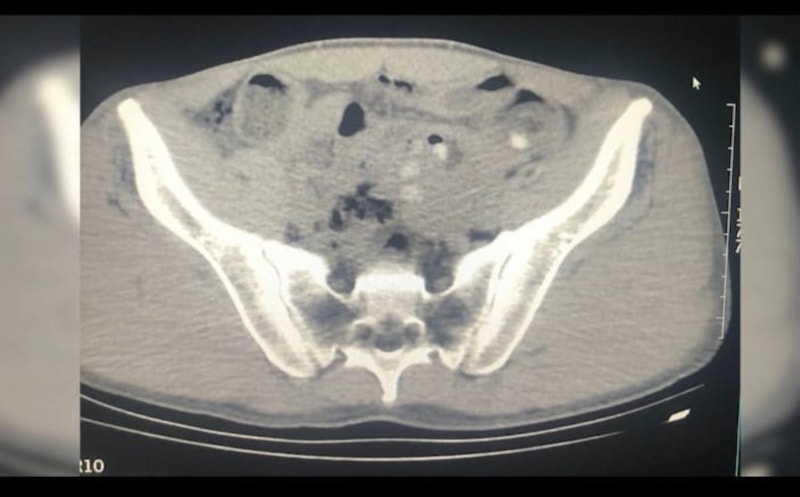

Gözaltına alınıp hastaneye götürülen şüphelilerin çekilen röntgenlerinde de midelerinde, 45 kapsül metamfetamin tespit edildi.

Şüphelilerin midesindeki uyuşturucu doğal yollarla çıkarıldı.